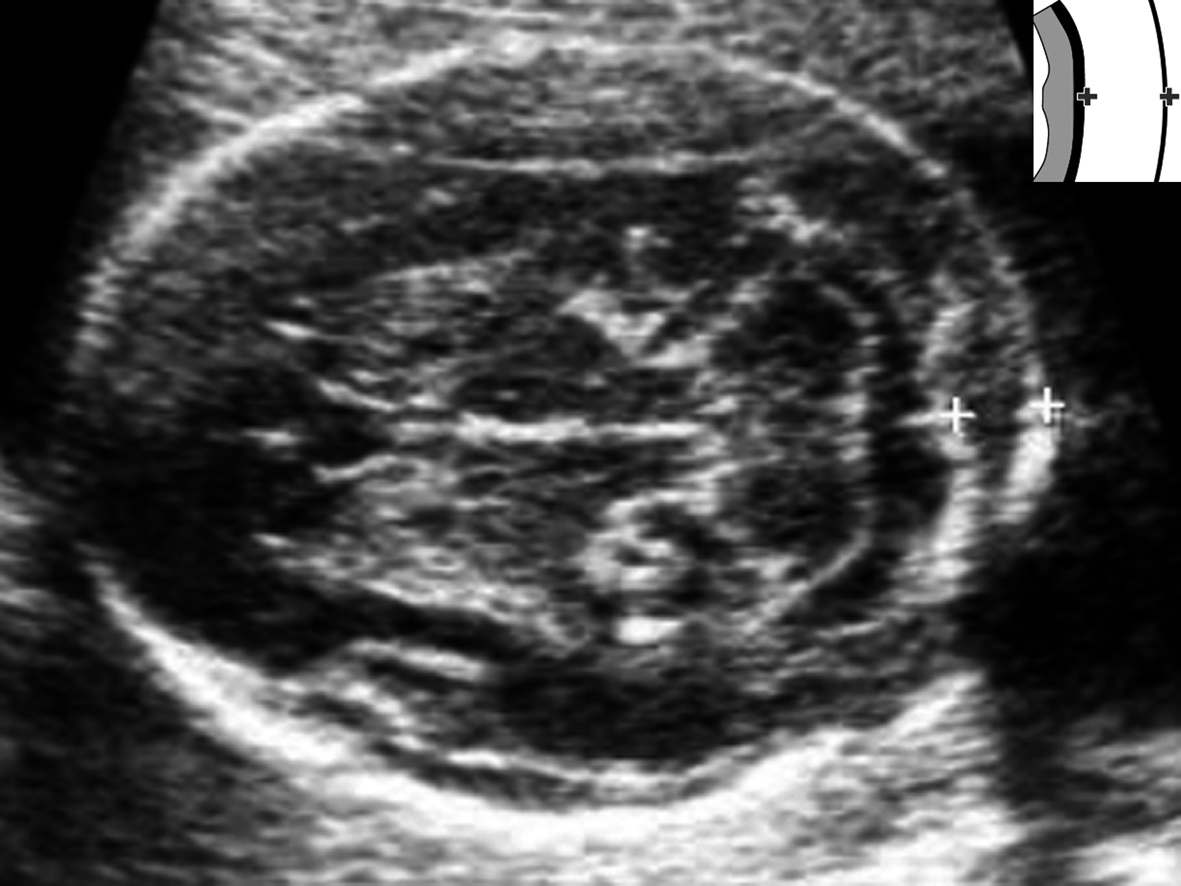

Benacerraff等在1985年提出了颈项透明层(nuchal translucency, NT)在早期妊娠胎儿和21-三体综合征之间的关联特性后,针对中期妊娠的胎儿,在1987年又提出了颈褶(nuchal skinfold thickness, NFT)(图2)与21-三体综合征的关系,并采用≤6mm作为15~20周胎儿的界限值;国内有研究者统计、汇总了12~40孕周胎儿的NFT参考值。Tannirandorn等根据2114例染色体正常胎儿资料提出了16~24孕周胎儿颈褶厚度与孕龄的关系:

NFT (mm) = -0.502 + 0.212 GA(周)(r = 0.36, P< 0.001)

用以评价中期妊娠不同孕周胎儿颈褶厚度,但他们没有获得预期的应用效果。因此,Tannirandorn等的资料以及Grandjean等进行的多中心研究资料表明,使用胎儿颈褶厚度作为21-三体综合征的评价方法还需要进一步的研究。

图2胎儿颈项颈褶测量(测量标记+之间为胎儿颈项颈褶)